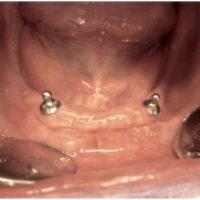

Denne løsning fungerer ved, at der indsættes implantater i kæben, der fungerer som en tryklås. På protesens bund sidder der en trykknap, som ´knappes´ fast på implantatet. Det sikrer, at protesen sidder helt fast i munden, selvom du ikke har egne tænder at sætte den fast på. Drejer det sig om en protese i overmunden, er der desuden den fordel, at din udtale bevares samt følelsen af at smagsoplevelsen bliver bedre , da protesen så kan blive ganefri.